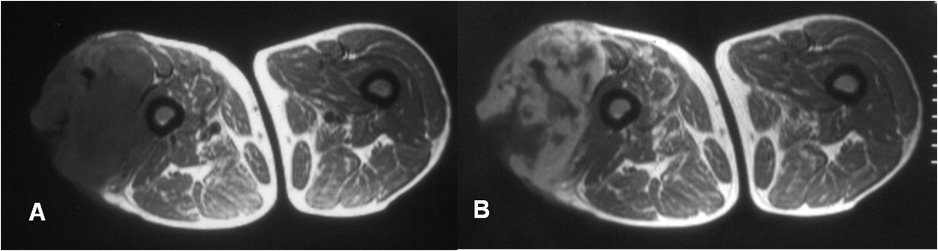

Tiene las características de lesión agresiva, de localización metafisodiafisiaria y con clínica y hallazgos similares al sarcoma pleomórfico indiferenciado, no pudiendo ser diferenciado por imágenes. (23, 26). (Fig 107 B).

Fig 107 B. Fibrosarcoma.

A: RM axial en T1 simple y B: RM axial en T1 con contraste. Imagen hipointensa y con realce heterogéneo del contraste, que ocupa la región lateral del muslo. Esta lesión cruza compartimientos y crece por infiltración, correspondiendo a fibrosarcoma.